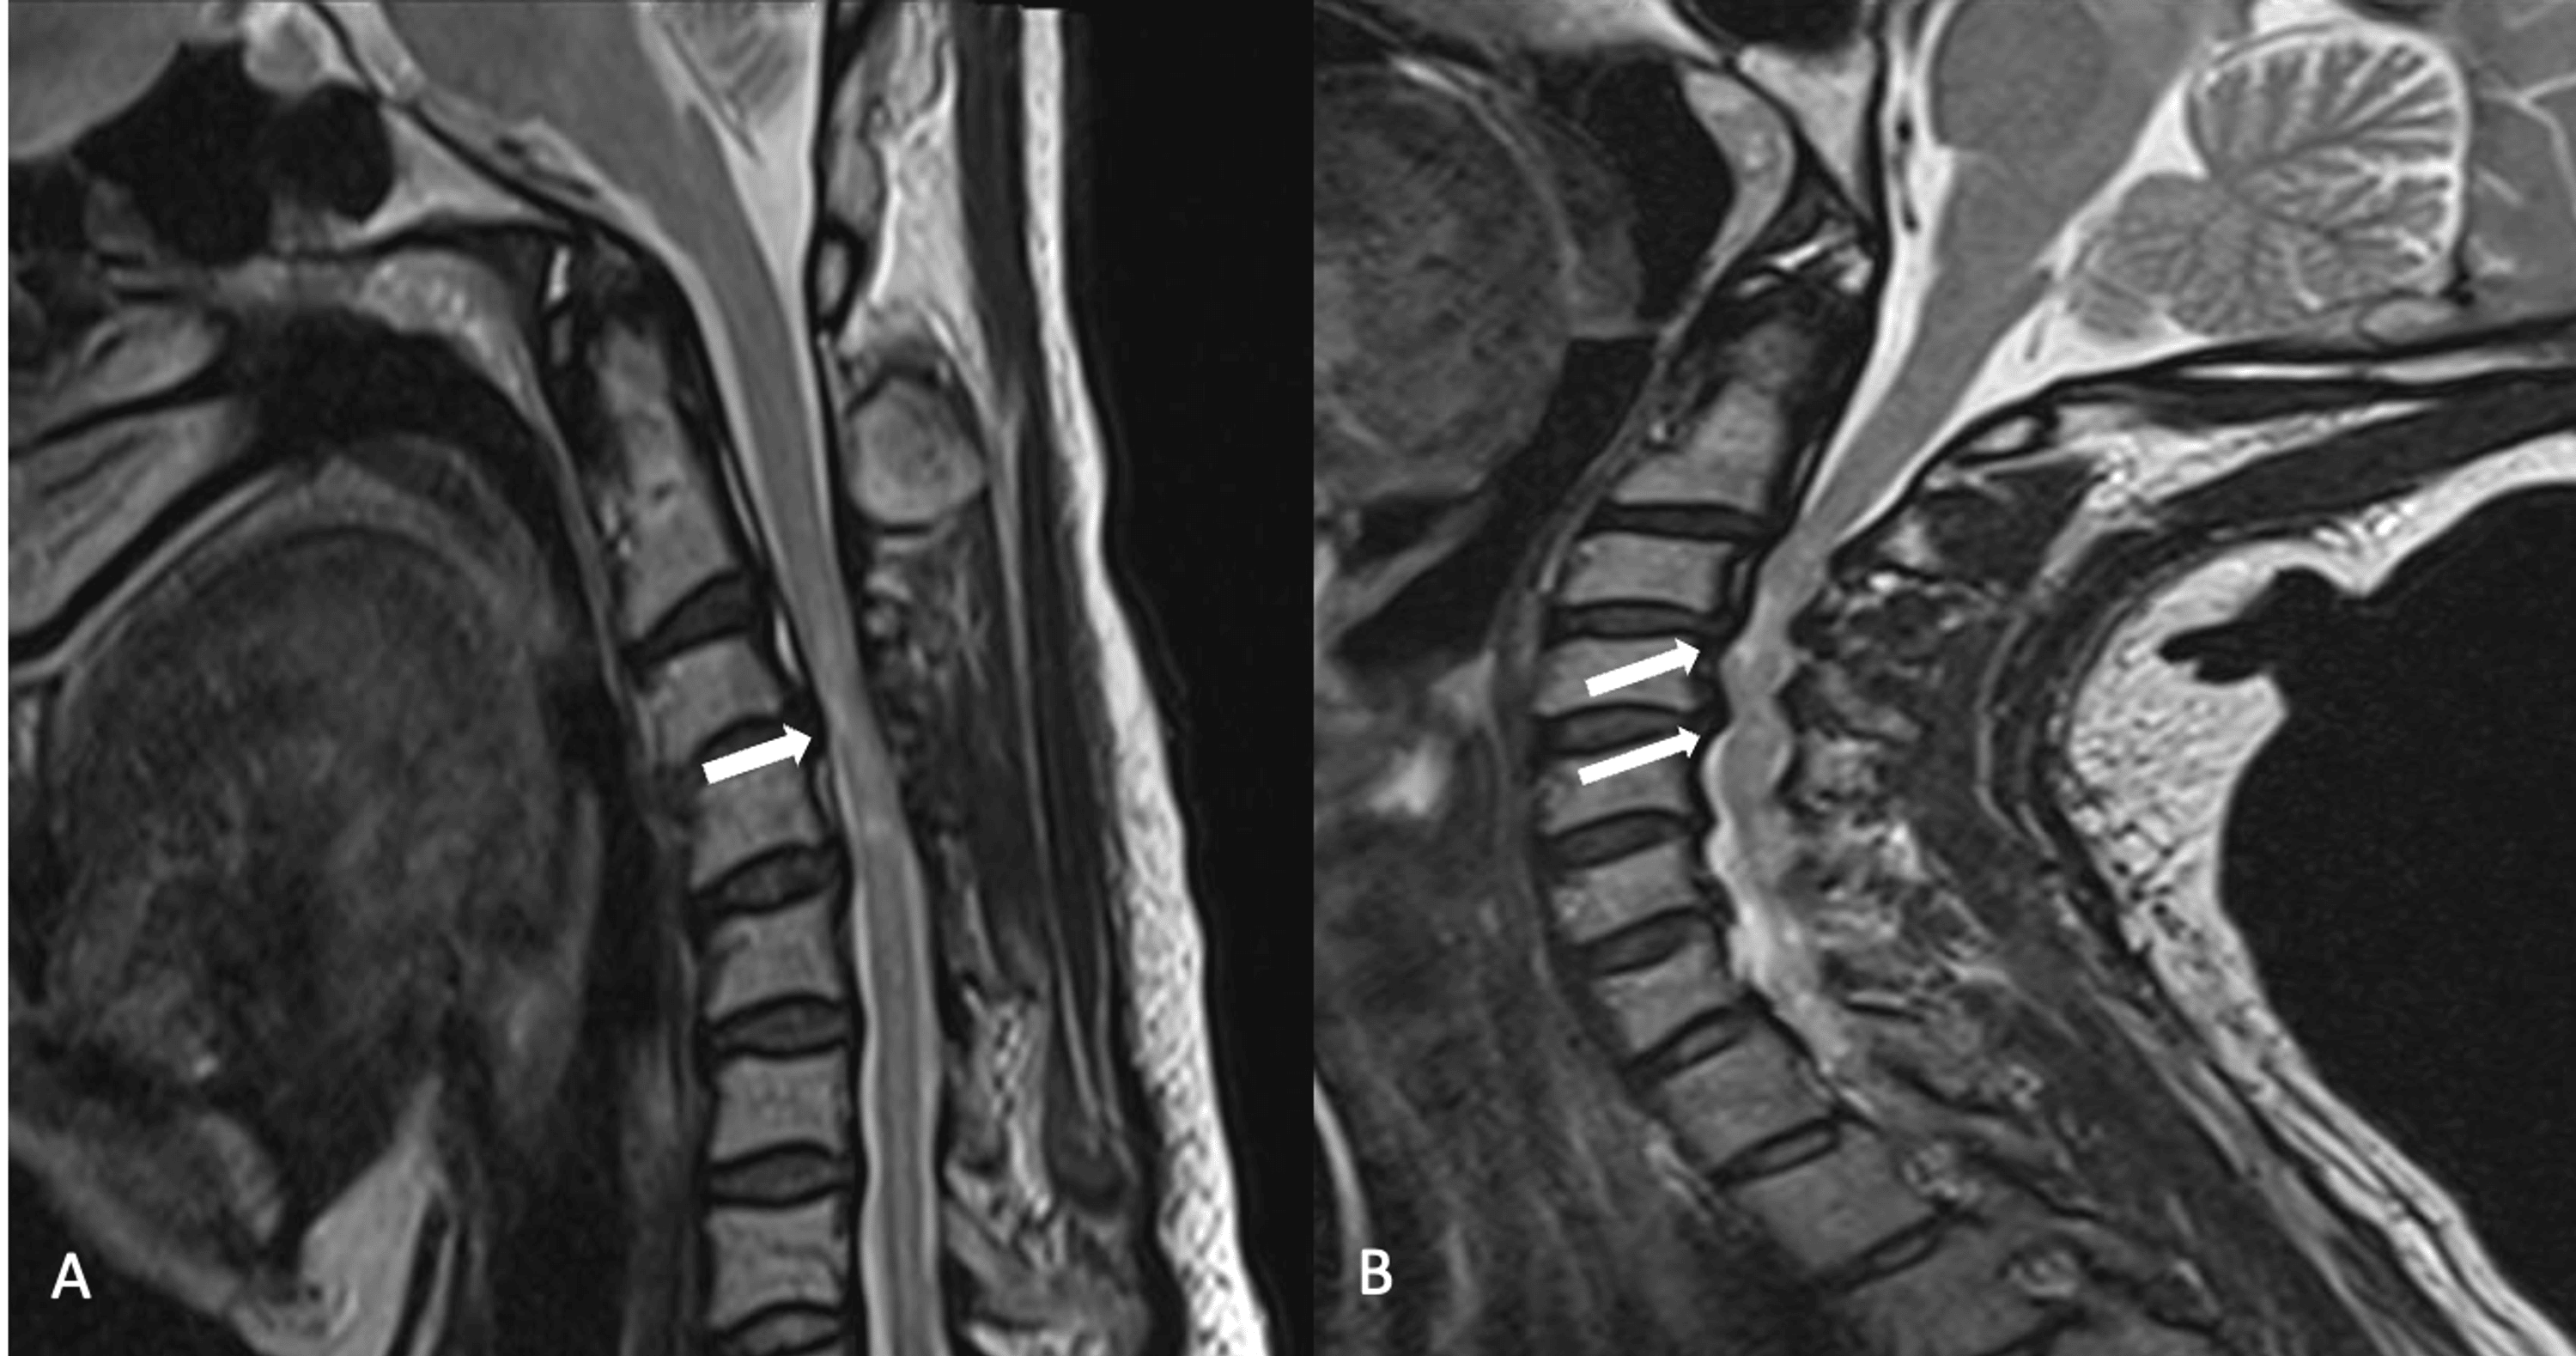

Two positioned MRI at full extension (a) and deep flexion (b Tape Extensions Mri Profound artifact on mri from artifact from the patient's hair extensions. While hair extensions can affect an mri scan, the level of interference depends on the type of extensions you have. Metallic foreign objects can cause various thermal injuries in patients undergoing magnetic resonance imaging (mri). Metallic foreign objects can cause various thermal injuries in patients undergoing magnetic resonance imaging. Tape Extensions Mri.

Cureus Utility of Flexion and Extension MRI for Evaluating Isolated Tape Extensions Mri Hair extensions, which transform even the thinnest head of hair into a luxurious mane by adding volume and length, are now quite the rage. 1 article features images from this case. Metallic foreign objects can cause various thermal injuries in patients undergoing magnetic resonance imaging (mri). Metallic foreign objects can cause various thermal injuries in patients undergoing magnetic resonance imaging. Tape Extensions Mri.